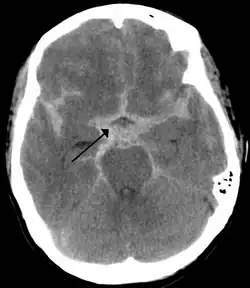

| CT scan of the brain showing subarachnoid hemorrhage as a white area in the center (marked by the arrow) and stretching into the sulci to either side | |